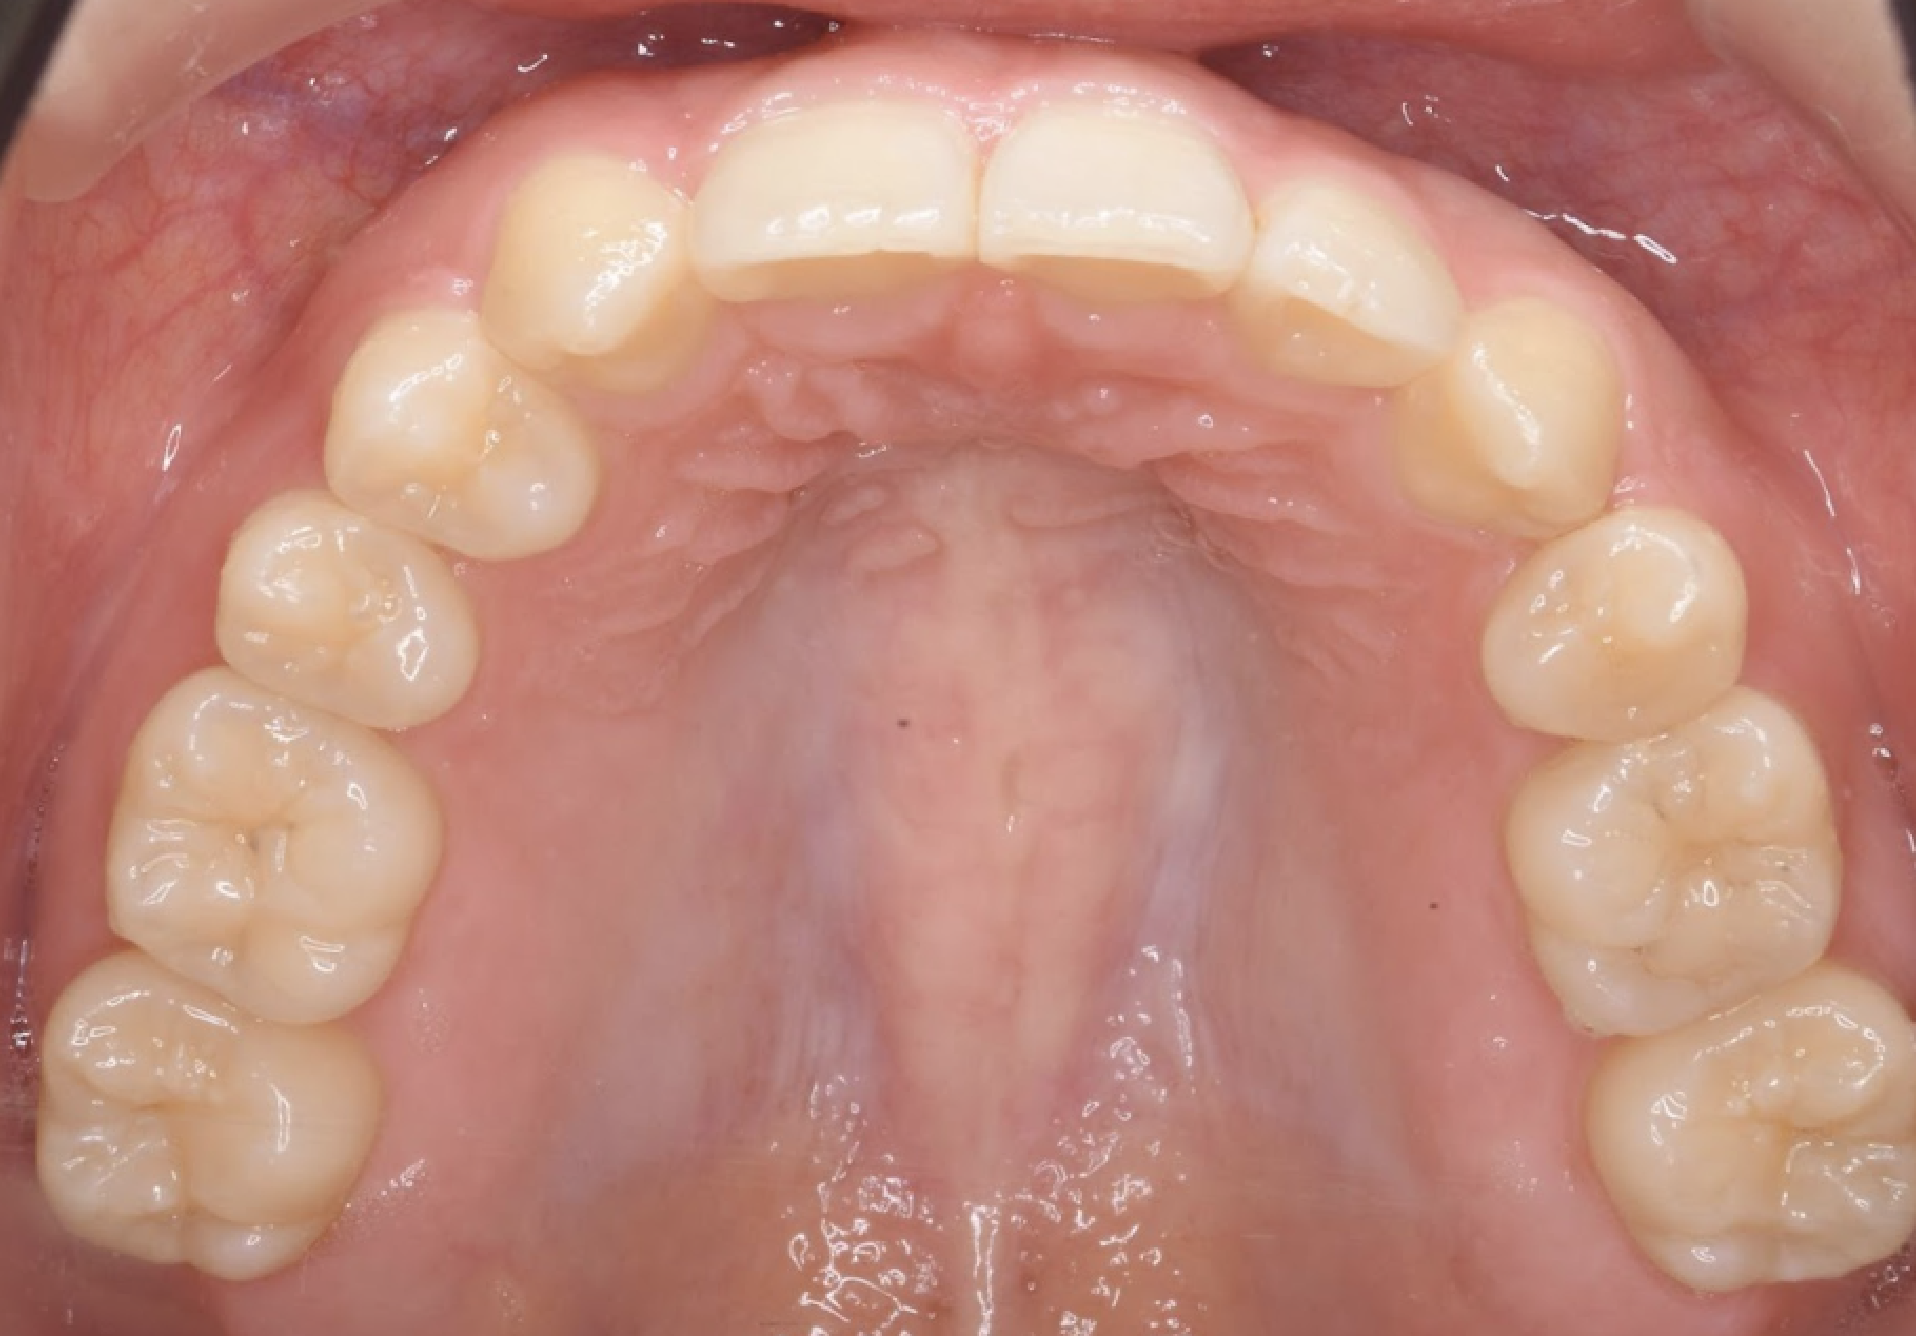

治療後の口腔写真

After